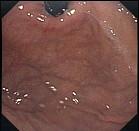

问题 男,23岁,食用海鲜后,出现腹痛、腹胀2天,呕吐,查体,无发热,下肢可见皮疹,B超肝胆正常,胃镜检查如图。最可能的诊断是 ( )

选项 A、阑尾炎 B、消化道出血 C、急性胰腺炎 D、过敏性紫癜 E、急性胆囊炎

答案 D